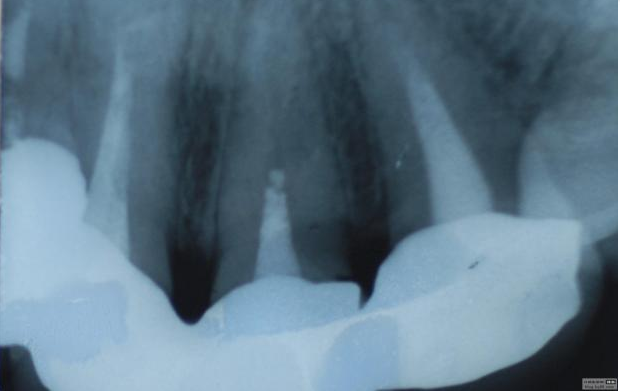

最近接到這樣一位患者,上前牙氧化鋯聯(lián)冠修復(fù)不足一年時(shí)間,現(xiàn)患者主訴左上前牙疼痛來診,檢查發(fā)現(xiàn)上前牙冷熱無反應(yīng),扣診(++),牙齦紅腫,探出血,冠邊緣不密合, X片示基牙全部已做根管治療,但是根管充填全部欠填。

病例1 由于根管充填不完善造成修復(fù)體拆除

修復(fù)后出現(xiàn)根尖周炎癥狀 根管再治療后病變愈合